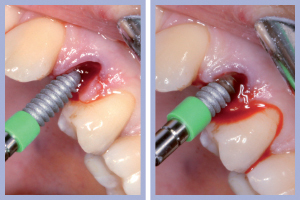

- Figg. 15a, b – Inserimento e preparazione del moncone temporaneo di destra

- Figg. 16a, b – Consegna della corona provvisoria in resina di destra

- Figg. 17a, b – Inserimento e preparazione del moncone temporaneo di sinistra

- Fig. 18 – Consegna della corona provvisoria in resina di sinistra

– Posizionamento e preparazione dei monconi temporanei (Figg. 15-20);

– Adattamento e consegna delle corone provvisorie (Figg. 15-20).

Il posizionamento implantare è stato seguito dal posizionamento e dalla preparazione intra-orale dei monconi temporanei e dalla successiva consegna, previa ribasatura, delle corone provvisorie. Durante la fase di attesa dell’osteointegrazione degli impianti si procedeva alla preparazione protesica dei canini (nella posizione dei laterali) per ottenere, tramite ricopertura protesica, la forma degli incisivi laterali.